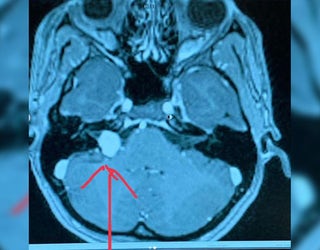

Wife Of Lions Qb Matthew Stafford Has Brain Tumor Needs Surgery

Wife Of Lions Quarterback Matthew Stafford Has Brain Tumor

Kelly Stafford Wife Of Nfl Qb Matthew Stafford Has Brain Tumor

Wife Of Detroit Lions Quarterback Matthew Stafford Reveals She Has

Wife Of Lions Quarterback Matthew Stafford Has Brain Tumor Keci